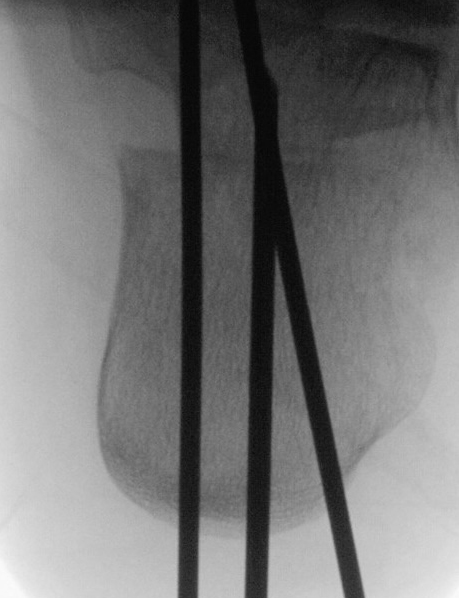

Liegt eine stark subduktische 5. Zehenposition vor, fräsen wir bevorzugt in der Kramertechnik für eine maximale Korrektur und Setzen für zwei bis drei Wochen einen intramedullären Draht nach proximal durch die Osteotomie (Abb. 27).

Abb. 27 a-d: Radiologische Darstellung intraoperativ (a) und vor dem Entfernen des Drahtes einer kompletten Schaftosteotomie mit intramedullärem Draht stabilisiert (b). Die Osteotomie wird minimalinvasiv durchgeführt und der Draht nach der Spülung über den gleichen Hautschnitt einfach in den Schaft hineingeschoben und die Osteotomie darüber stabilisiert. Das Köpfchen kann anschließend je nach Bedarf plantarisiert oder extendiert werden. Radiologische Verlaufskontrolle vor Entfernung des Drahtes (c-d).